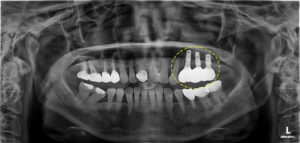

반대쪽과 비교해 보시면

상악동 거상술을 진행한 부위가 하얗게

뼈로 찬 모습을 보실 수 있는데요.

임플란트가 식립될 공간이 충분히 확보되어

다행히 부작용 없이 안정적으로

식립되었어요.👏👏